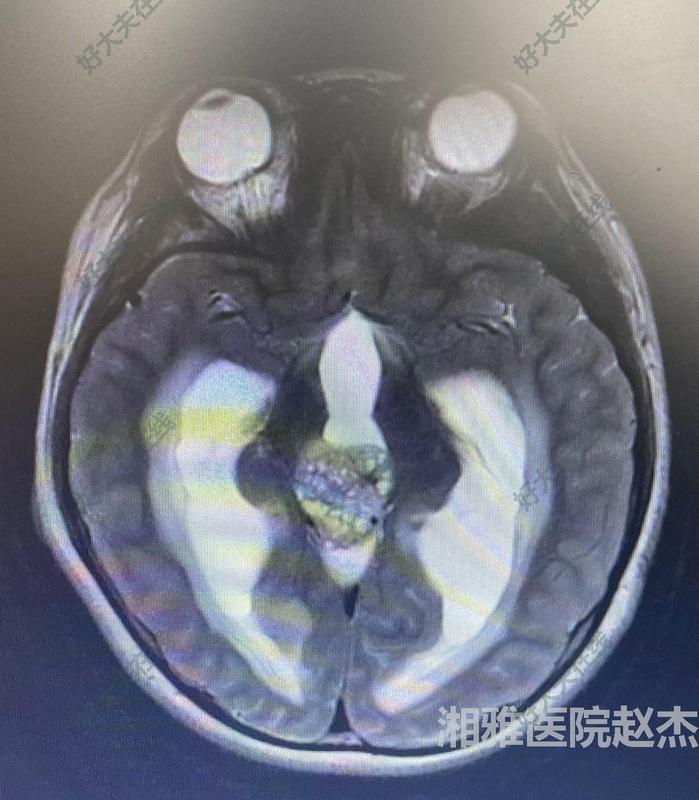

治療前男,9歲,因頭痛伴惡心嘔吐20余天入院。入院查體:神清,急性病容。頭部磁共振顯示:松果體區(qū)占位。抽血查HCG正常,血AFP18.52nh/ml(0-2.00)術(shù)前診斷考慮:松果體區(qū)占位:生殖細(xì)胞腫瘤可能性大。梗阻性腦積水。治療中經(jīng)兒童腦腫瘤多學(xué)科討論后認(rèn)為可以直接手術(shù)切除。遂實(shí)施開顱手術(shù)切除病變。手術(shù)采用經(jīng)幕下小腦上入路,顯微鏡下全切除病變。病理為混合生殖細(xì)胞腫瘤。術(shù)后建議輔助治療。出院時(shí)神清語(yǔ)利,四肢活動(dòng)好。治療后治療后6月恢復(fù)良好。完成放射治療。頭部及全脊柱脊髓磁共振掃描未見復(fù)發(fā)。